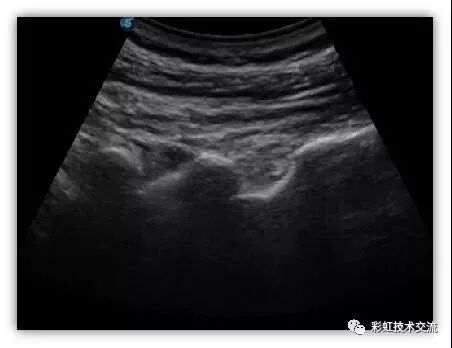

腰椎小关节

(2)摇:整个超声探头平面紧贴受检区域皮肤,以超声探头与胸壁的接触点为支点,将超声探头左右摇摆,观察整个切面。